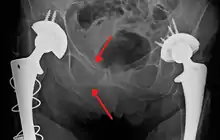

FractureRtSandIRami(Sin2).png

An X-ray showing a fracture of the inferior and superior pubic rami in a patient with previous hip replacements

One of the primary concerns is the risk of pelvic fracture, which itself is associated with a myriad of complications including bleeding, damage to the urethra and bladder, and nerve damage.[29] If pelvic trauma is suspected, emergency medical services personnel may place a pelvic binder on patients to stabilize the patient's pelvis and prevent further damage to these structures while patients are transported to a hospital. During the evaluation of trauma patients in an emergency department, the stability of the pelvis is typically assessed by the healthcare provider to determine whether fracture may have occurred. Providers may then decide to order imaging such as an X-ray or CT scan to detect fractures; however, if there is concern for life-threatening bleeding, patients should receive an X-ray of the pelvis.[30] Following initial treatment of the patient, fractures may need to be treated surgically if significant, while some minor fractures may heal without requiring surgery.[27]